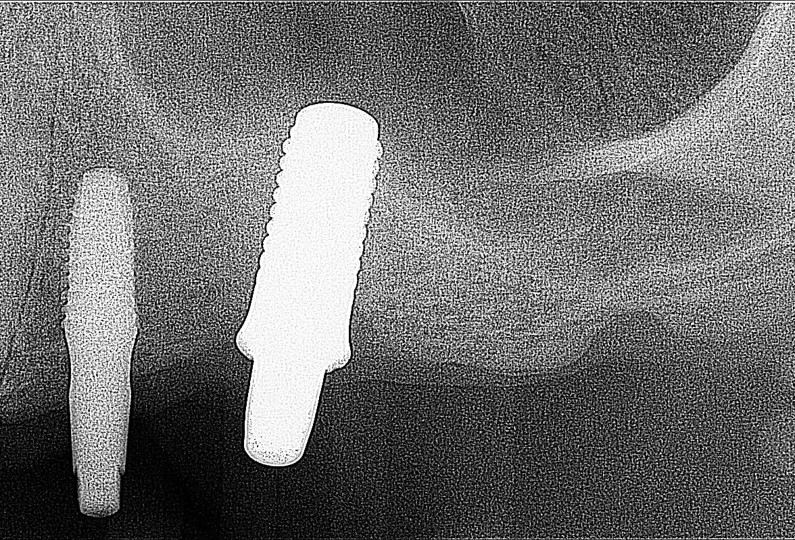

A dental Implant is a titanium “root” that integrates directly with the surrounding bone and replaces the function of the natural tooth. Neoss Implants are made using the best quality medical grade titanium, which is well known for its proven biocompatibility, and have a treated surface to facilitate bone integration.